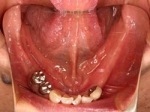

片側2歯欠損片側2歯欠損片側2歯欠損 主訴-入れ歯を使ってみたが違和感強くてダメ。固定のものにしたい。術前下顎口腔内(鏡像) 二次オペ時(鏡像)二次オペ時(鏡像)二次オペ時(鏡像) 術後術後術後、左下奥2本インプラント(鏡像) 術後(レントゲン)術後(レントゲン)術後(レントゲン)、左下奥2本インプラント

両側5歯症例

両側5歯症例両側5歯症例両側5歯症例 主訴-義歯のバネが壊れて手前の歯が痛んできた。 術前(旧義歯装着、鏡像) 術前(下顎粘膜面、鏡像)術前(下顎粘膜面、鏡像)術前(下顎粘膜面、鏡像) 術前レントゲン術前レントゲン術前レントゲン 術前口腔内(正面観)術前口腔内(正面観)術前口腔内(正面観)

術後(鏡像)術後(鏡像)術後(鏡像) 術後口腔内(正面観)術後口腔内(正面観)術後口腔内(正面観)もう入れ歯は要らなくなりました。 術後レントゲン術後レントゲン術後レントゲン